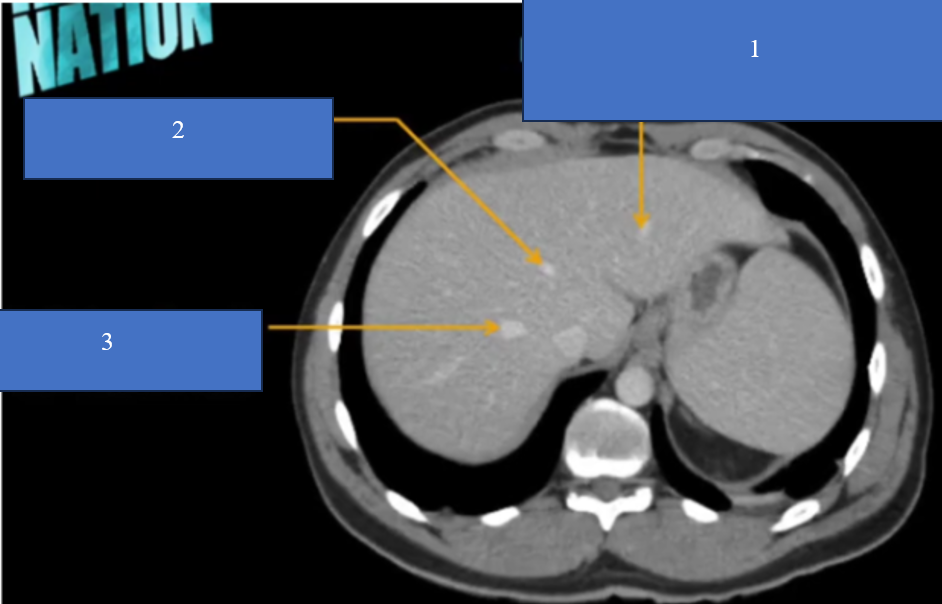

TM gan ở đâu? TM chủ dưới ? ĐM chủ?